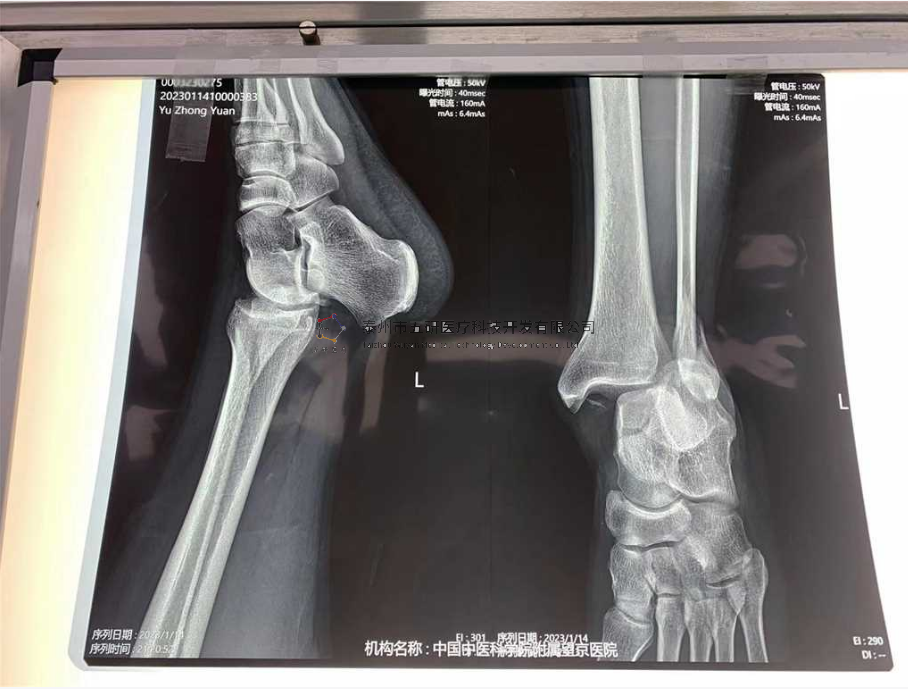

// 踝關(guān)節(jié)

本病例由中國中醫(yī)科學(xué)院望京醫(yī)院骨關(guān)二提供(術(shù)者:支架主任蔣主任)

【基本資料】患者,男,41歲

本病例踝關(guān)節(jié)骨折。手術(shù)名稱:左踝關(guān)節(jié)骨折外固定支架手術(shù)

【治療前影像】